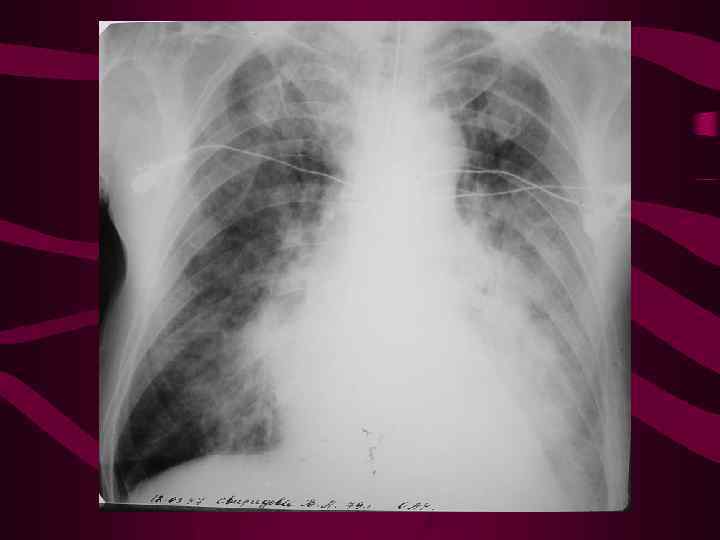

4 - альвеолярный отек легких Изменения соответствуют среднему давлению в левом предсердии свыше 35 мм рт. ст. На фоне венозного застоя с признаками интерстициального отека определяются множетсвенные сливающиеся, разной величины очаговые тени в легких за счет скопления эксудата в альвеолах. Очаговость имеет неравномерную интенсивность и нечеткие очертания, может быть симметричной, двухсторонней, но может быть и односторонней. Нередко выпот в плевральных полостях.

4 - альвеолярный отек легких Изменения соответствуют среднему давлению в левом предсердии свыше 35 мм рт. ст. На фоне венозного застоя с признаками интерстициального отека определяются множетсвенные сливающиеся, разной величины очаговые тени в легких за счет скопления эксудата в альвеолах. Очаговость имеет неравномерную интенсивность и нечеткие очертания, может быть симметричной, двухсторонней, но может быть и односторонней. Нередко выпот в плевральных полостях.